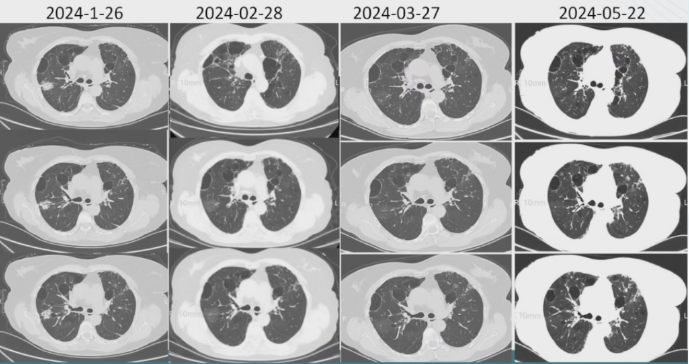

9. 胸部CT2024-01-26

胸廓基本对称,双肺内示片状及网格样高密度影116片未见明显改变,各主支气管开口通畅,双肺内散在低密度影纵隔内未见明显肿大淋巴结(图2)

图片

2  患者胸部CT对比

【出院后1个月】2024年2月28日,查CRP 34.42 mg/L。胸部CT(图3):胸廓基本对称,双肺内片见状及网格样高密度影,右肺部分病变较前密度减低,各主支气管开口通畅,双肺内示散在低密度影;纵隔内未见明显肿大淋巴结,前纵隔内示约0.9 cm×0.5 cm结节影,边界清晰,密度均匀。

3  患者随诊胸部CT与之前对比

【出院后2个月】2024年3月27日,CRP 2.04 mg/L。胸部CT(图4):胸廓基本对称,双肺网格样高密度影,双肺内散在低密度影;各主支气管开口通畅,纵隔内未见明显肿大淋巴结,前纵隔内示约0.9 cm×0.5 cm结节影,边界清晰,密度均匀。嘱继续口服艾沙康唑治疗。

4  患者随诊胸部CT对比

【出院4个月】2024年5月22日常规随诊,复查血常规,CRP 15.86 mg/L,其余无异常。胸部CT(图5):考虑双肺间质纤维化可能性大;肺气肿,肺大疱;双肺小结节;前纵隔结节;双侧胸膜增厚。患者艾沙康唑已服用4个月,肺部病灶吸收可,暂停用观察半月,如有不适,及时复查,3个复查胸部CT。

5  患者胸部CT变化